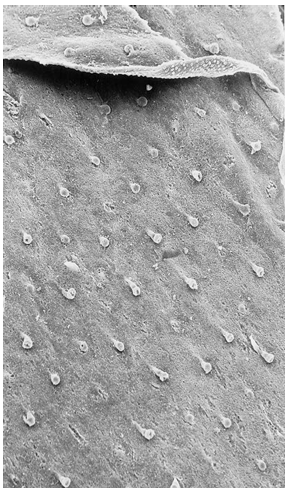

각질화도 특징적이에요

임신 중 가장 먼저 각질이 형성되는 곳은 손톱이고 임신 11주쯤 발견됩니다

일반적으로 두꺼운 피부부터 각질화가 진행됩니다